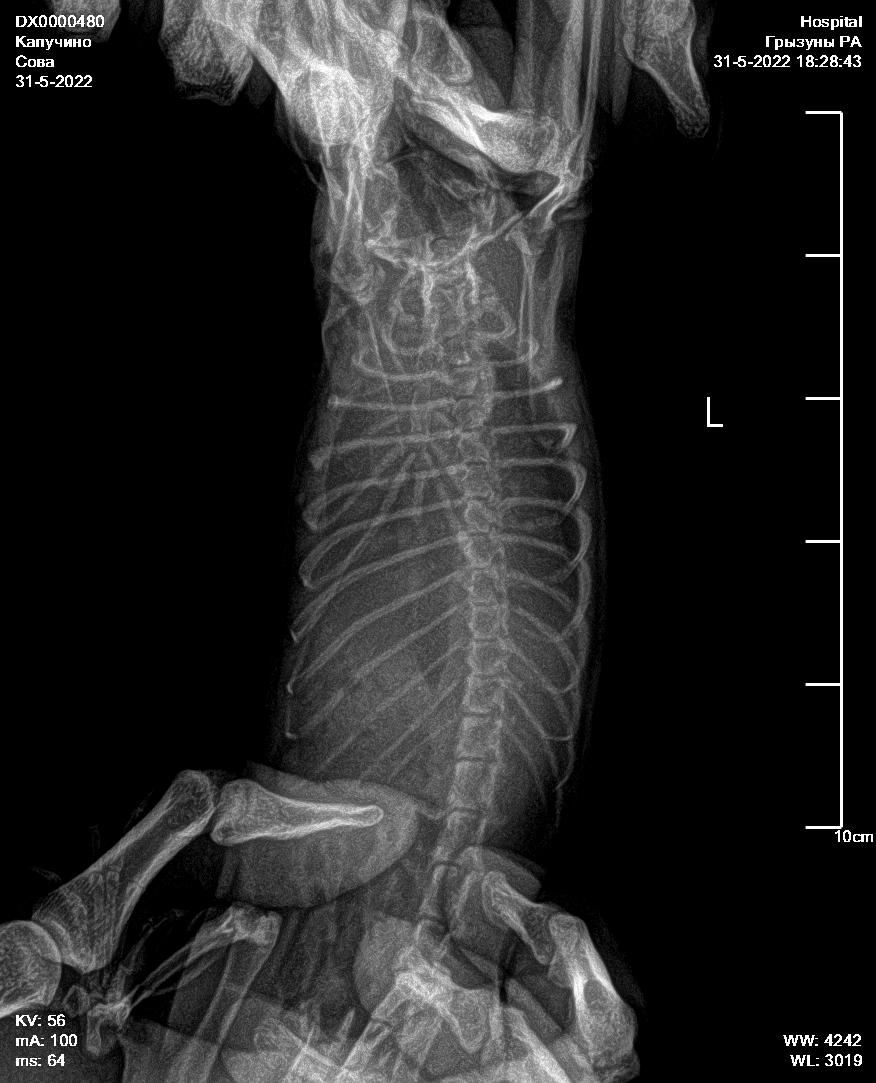

Город Волгодонск, девочка, 1 год. Тяжёлое дыхание, сделали рентген. В вк в домике крысы отдали снимки рентгенологу. С самого первого поста там прошёл почти месяц. По рентгену диагностировали большое количество жидкости в грудной клетке, структура легких уплотнена. Прописали Тилозин 0.05мл 2 раза в день на 5 дней посмотреть динамику. Сказали, что процесс необратим и лечить нечем. Находил на форуме похожие случаи, подскажите, что сделать, чтобы хотя бы стабилизировать и поддерживать состояние крысы? Она очень активная, с аппетитом всё хорошо. Только очень тяжёлое дыхание.